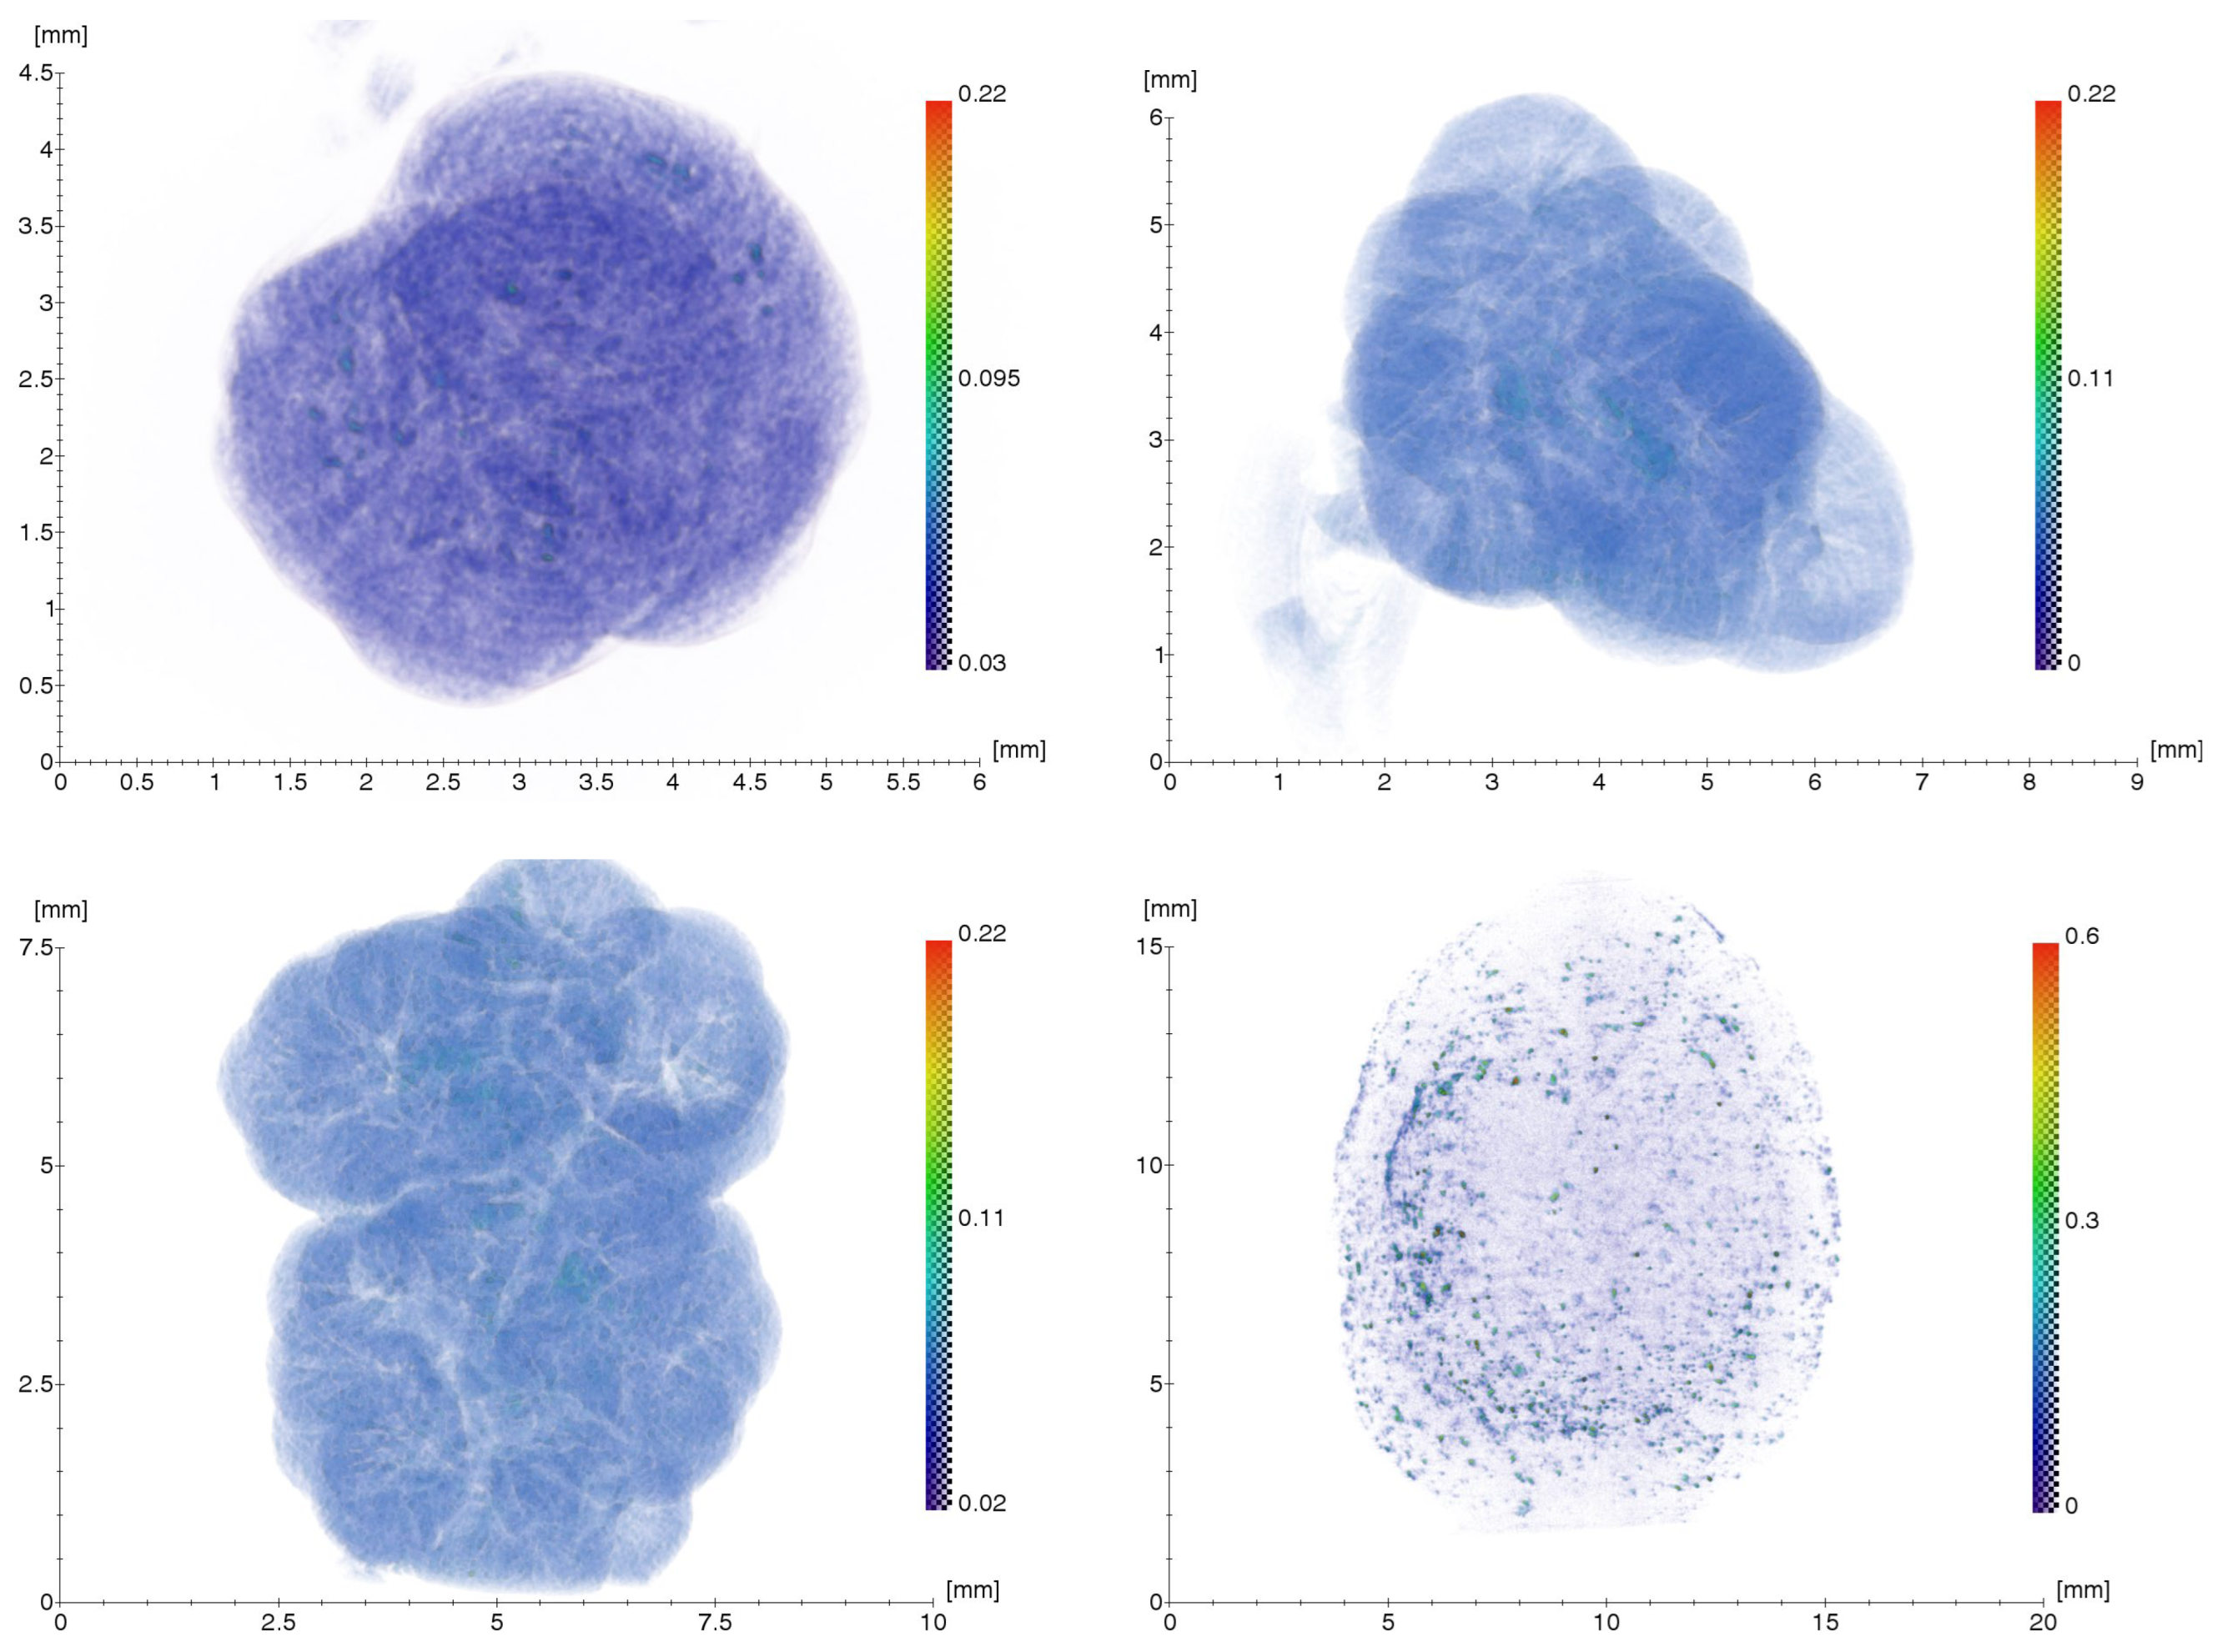

2.1.1. Results of X-ray and Electron Microscopic Studies

4.2. X-ray Microtomography (XMCT)

- Mo tube (focus size 12 × 0.4 mm), 40 kV × 40 mA mode;

- Monochromator—Pyrolytic graphite, reflection (0002);

- Wavelength—0.71 Å (E = 17.5 keV);

- Detector—Ximea XiRay11 (pixel size 9 × 9 microns, field of view 36 × 24 mm);

- Exposure—4 s per projection;

- Measuring range—800 projections in 0.25° increments (0°–200°).